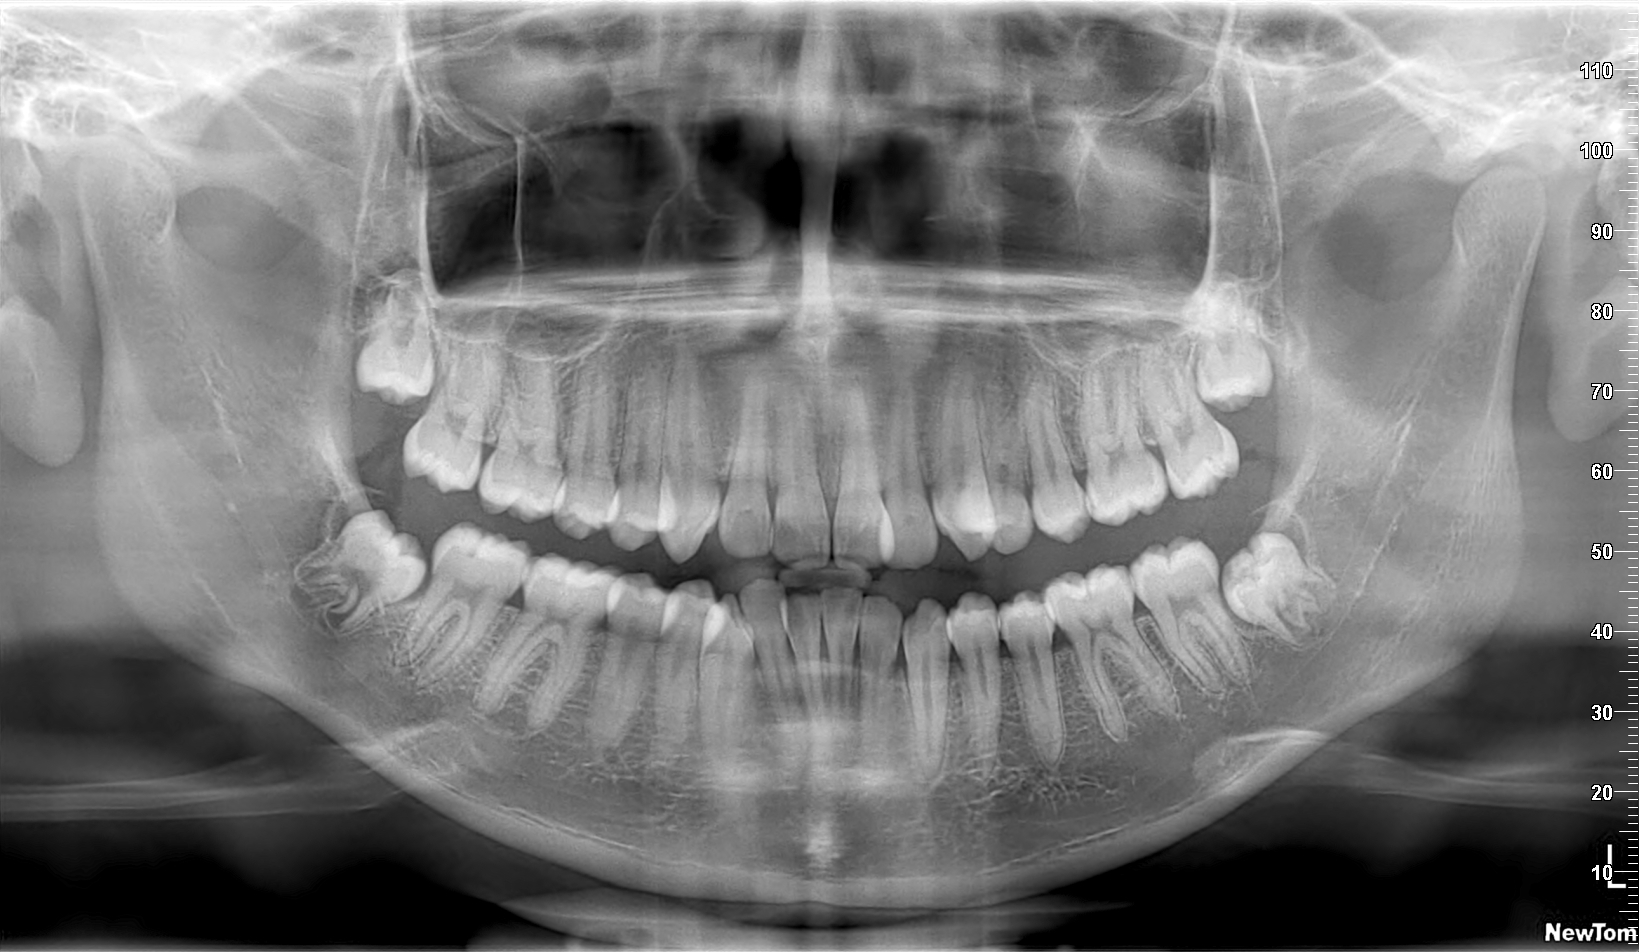

Tenezaca Guaman Geovany Patricio 2009 11 07 PAN05 4